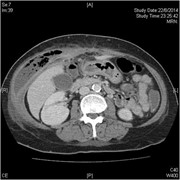

Concurrent hepatic hemangioma and solitary fibrous tumor: diagnosis and management

Michael Kueht and others

Journal of Surgical Case Reports, Volume 2015, Issue 7, July 2015, rjv089, https://doi.org/10.1093/jscr/rjv089